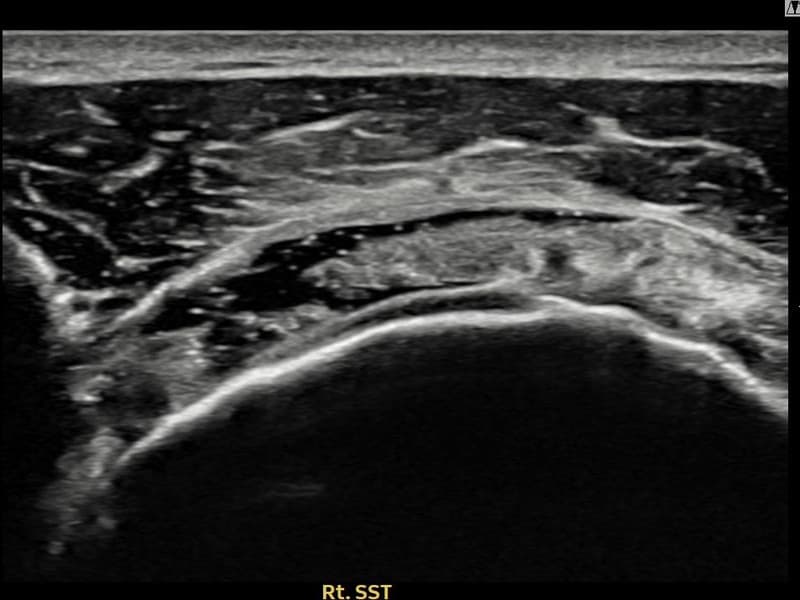

术前

术前超声确认右侧 冈上肌腱 관절면측 광범위 部分撕裂,右侧冈上肌腱回声不连续伴肌腱缺损(16mm × 5mm (肌腱厚度约75%缺损))。术后超声显示撕裂部位充满再生组织,肌腱连续性恢复,回声模式正常化。